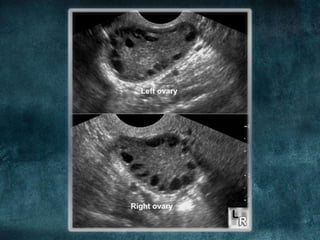

COMMENT THE

ULTRASOUND

FINDINGS?

WHAT IS THE SUGGESTIVE

AND HOW TO DIAGNOSE

2

HOW TO DIAGNOSE: PCOS

Rotterdam criteria for diagnosis

Two or more of the three following criteria:

• polycystic ovaries (either 12 or more peripheral follicles or

increased ovarian volume up to 10mm3)

1    • -via TVUS

• oligo- or anovulation (manifested as oligo- or amenorrhea)

• clinical and/or biochemical signs of hyperandrogenism.

3